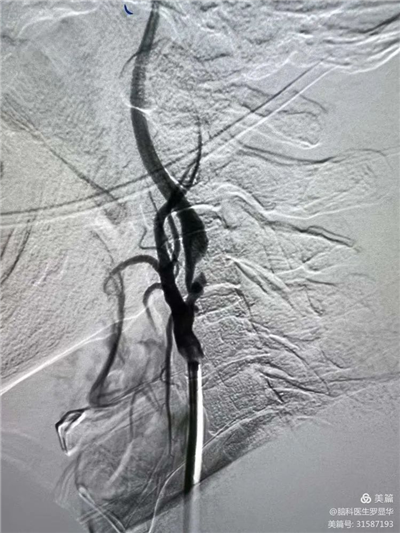

手术过程:指引导管到位

手术过程:球囊扩张后,protege支架到位

术后造影示狭窄解除